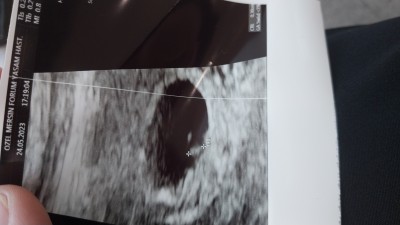

Kızlar bugun doktora gittim tek kese ama 2 goruntu var ikiz olabilir mi bitanenin kalbi atıyordu digeri bostu sonradan gelisir mi acaba doktor kendiliginden kaybolur gelismese hic yasayan oldu mu

Gebelik haftası 6+1

Yolk kesesi deniyo sanirim doktorunuz aciklamis zaten hanimefendi

O yolk kesesi bebis degil :)